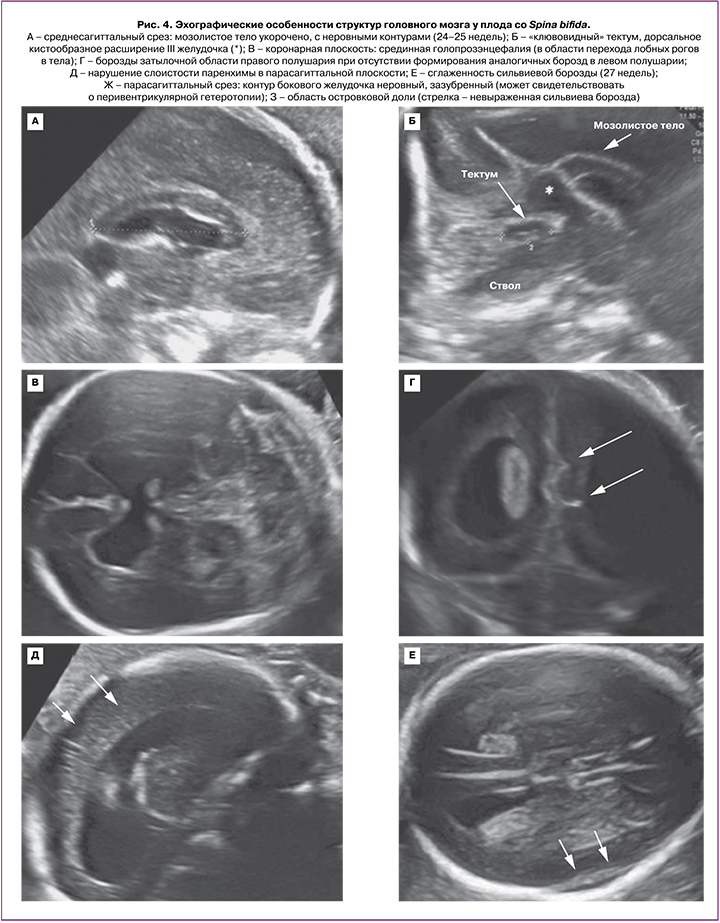

Во II триместре беременности во всех 20 случаях были выявлены общепринятые эхографические признаки Киари II: вклинение мозжечка в Большое затылочное отверстие с признаком его деформации (форма «банан»), изменение конфигурации костей черепа (форма «лимон»), вентрикуломегалия, наличие спинномозговой грыжи позвоночника. ММЦ и РШ определялись у 15/20 и 5/20 плодов соответственно. Начальный уровень расположения Spina Bifida по отношению к позвоночнику определялся у 2 плодов с позвонка T10, у 14 плодов – с L2–L3, у 4 – с L4–L5 (рис. 3). Средний срок беременности, когда проводилась детальная морфометрия церебральных структур, составил 23,9 (23,0–25,3) недель. Для 20 плодов были характерны изменения: вентрикуломегалия (10–17 мм независимо от уровня поражения спинного мозга), «клювовидный» тектум (крыша мозга), «заостренные» затылочные рога боковых желудочков, задержка формирования борозд (рис. 4, таблица). Средние значения ширины задних рогов боковых желудочков составляли: слева – 11,5 (9–16) мм, справа – 11 (5–17) мм. Дисгенезия мозолистого тела была выявлена у 3/20 пациентов. Для остальных 17 случаев было характерно незначительное укорочение длины мозолистого тела. Средние значения длины мозолистого тела составили 23,8 (14–29) мм (таблица). У половины плодов (55%) определялось дорсальное кистообразное расширение III желудочка. У 3 плодов из 20 с уровнем Spina Bifida L2–L3 была диагностирована межполушарная голопрозэнцефалия. При оценке тектума мы не выявили достоверно значимых различий в его длине по сравнению с нормативными значениями, однако у всех плодов была изменена его форма и расположение. Средние значения длины тектума составили 11,1 (9,5–14) мм. Лишь у 5/20 (25%) плодов длина тектума была более 11 мм, что соответствует более 2 стандартных отклонений для срока беременности 24–25 недель согласно исследованию Leibovitz Z. et al. [12]. У 80% (16/20) пациентов отмечалось нарушение формирования борозд островковых долей при типичном формировании остальных борозд полушарий мозга.

По данным нашего исследования, у всех плодов была выявлена особенность развития мозолистого тела, проявляющаяся дисгенезией, частичной агенезией и, в большинстве случаев, незначительным укорочением его длины. Обнаруженные у плодов «заостренные» задние рога боковых желудочков с уменьшением расстояния между его контуром и затылочной костью, а также межполушарные кисты (в 50% случаев), являющиеся задним и верхним продолжением третьего желудочка, подтверждают теорию дефицита белого вещества задних отделов, по сравнению с передними. Эхографическим подтверждением эмбрионально заложенной диспластической мальформации головного мозга при Киари II также является обнаруженная нами межполушарная голопрозэнцефалия у 15% (3/20) плодов.

Корковая мальформация при Киари II преобладает в задней медиальной части полушарий, где дефект белого вещества наиболее заметен. Еще в 1986 г. Gilbert et al. в патологоанатомическом исследовании 25 умерших детей с Киари II обнаружили мальформацию коры их головного мозга в 92% случаев: незрелое развитие – у 24%, нарушение слоистости паренхимы – у 24%, гетеротопию, истинное нарушение миграции нейронов – у 44%, полимикрогирию – у 40% пациентов [25]. Наиболее распространенная аномалия описывается в литературе, как стеногирия (что означает узкие извилины, от греческого stenos: узкий), характеризующаяся наличием многочисленных мелких уплотненных извилин с неглубокими бороздами, преимущественно в слаборазвитой задней медиальной части полушарий. Вышеописанные признаки согласуются с результатами нашего исследования, в котором задержка формирования борозд была выявлена в 100% случаев. Кроме того, у 80% плодов была выявлена аномальная сулькация островковых долей, подтвержденная постнатально, что не было ранее описано в мировой литературе.

Другой характерной особенностью мозговой организации при Киари II является изменение конфигурации «крыши» мозга – тектума, отвечающего за зрительные и слуховые рефлексы и коррелирующего, по некоторым данным, с выраженностью глазодвигательных нарушений при Spina Bifida [8]. В 2014 г. Leibovitz Z. et al. применили разработанные ими нормограммы среднего (midbrain) и заднего (hindbrain) отделов мозга у плодов с аномалией задней черепной ямки, в том числе с Киари II, и выявили ряд особенностей: удлинение тектума с формированием «клюва» и уменьшение переднезаднего диаметра среднего мозга более чем на 2 стандартных отклонения [12, 13]. В нашем исследовании у всех плодов с Киари II был выявлен «клювовидный» тектум. Однако в большинстве случаев размеры данной структуры не выходили за пределы нормативных значений. Лишь в четверти случаев длина тектума была увеличена и составляла более 12 мм, что выходило за рамки двух стандартных отклонений по нормативной шкале, разработанной Leibovitz Z. et al.